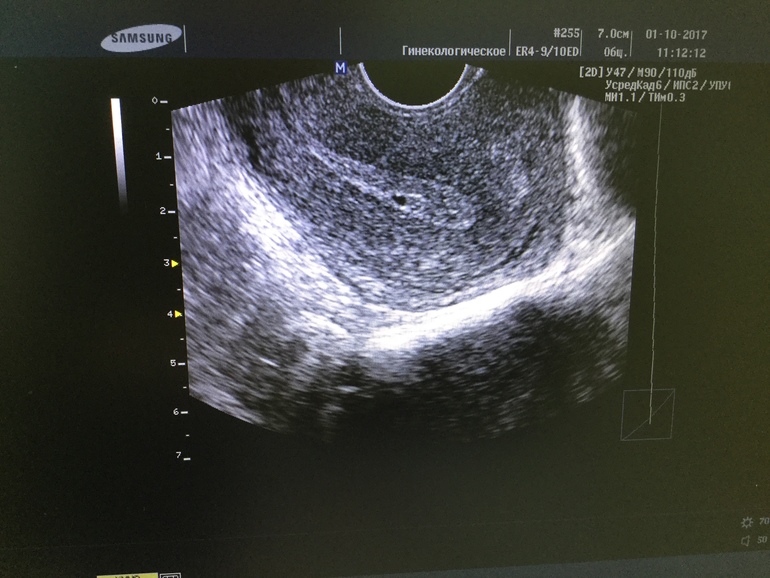

В течении дня на Узи схожу хоть гляну что там. Потом буду решать чего ждать